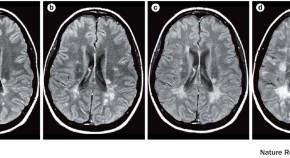

Myelin oligodendrocyte glycoprotein antibody-associated disease is an immune-mediated demyelinating disease that is distinct from multiple sclerosis but shares some of its characteristics. This Expert Recommendation, based on a Magnetic Resonance Imaging in MS workshop, proposes a diagnostic algorithm for the differential diagnosis of myelin oligodendrocyte glycoprotein antibody-associated disease and multiple sclerosis, using serological, imaging and clinical features.